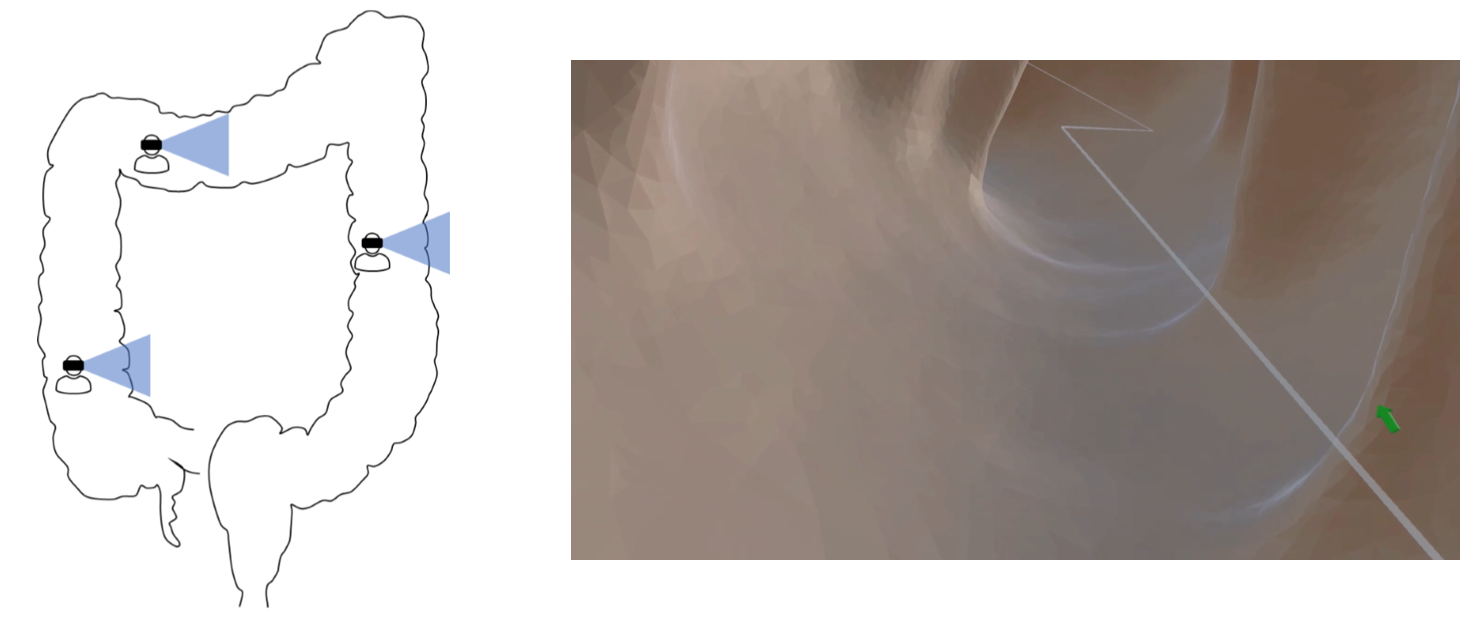

Each technique differs on how the user’s orientation is represented within the virtual environment. Identical to conventional CTC, the Fly-Through will make the user feel inside a cave. In this technique, the virtual camera follows the path without the need for users to move their head. They can, however, move their heads to see what is behind, below or above them. User orientation follows the centerline’s direction, facing the center of the colon throughout the tortuous tubular structure (Figure 4(a)). Differently from the traditional Fly-Over technique found in the literature hassouna2006flyover there is no need to split the colon in two halves and assign a virtual camera to each part. In this case, the inspection of the colon’s walls is done by users’ head movement. The camera will automatically keep the perpendicular perspective in the eyes of the users, facing the colon’s wall, while they can move their heads to analyze their surroundings as they move along the centerline (Figure 4(b)). Finally, the Elevator technique does not change camera orientation, in order to match the user’s real orientation (Figure 4(c)). In this sense, the user will be facing the walls in ascending and descending segments of the colon, only facing the center of the colon whenever the centerline’s orientation meets the user’s real orientation. Ultimately, this could reduce cybersickness during the VR trip, at the cost of increasing users’ chances of losing the sense of direction.

Refer to caption

(a) Fly-Through

(b) Fly-Over

(c) Elevator

Figure 4: Camera orientation schematics (left) and viewpoints (right) during (a) Fly-Through, (b) Fly-Over and (c) Elevator techniques.